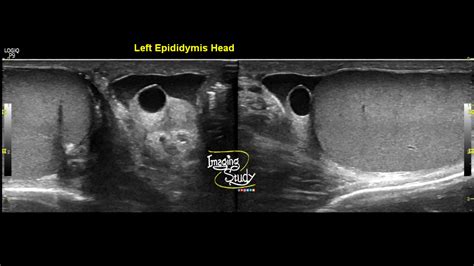

When you visit a healthcare provider, they will not rely on visual comparisons alone. Instead, they will use specific diagnostic tools to get a clear picture of what is occurring inside the scrotum. The gold standard for examining scrotal masses is a scrotal ultrasound. This painless, non-invasive test uses high-frequency sound waves to create detailed images of the testicles and the surrounding structures.

An ultrasound allows the physician to clearly distinguish between a solid mass—which requires further investigation—and a fluid-filled cyst, which is typically benign. If you have been looking for Testicular Cyst Images, you have likely seen ultrasound depictions showing dark, well-defined areas; these represent the fluid within the cyst, contrasting with the more textured appearance of the testicle itself.

Scrotal Ultrasound Imaging using sound waves Differentiates between solid masses and fluid-filled cysts.